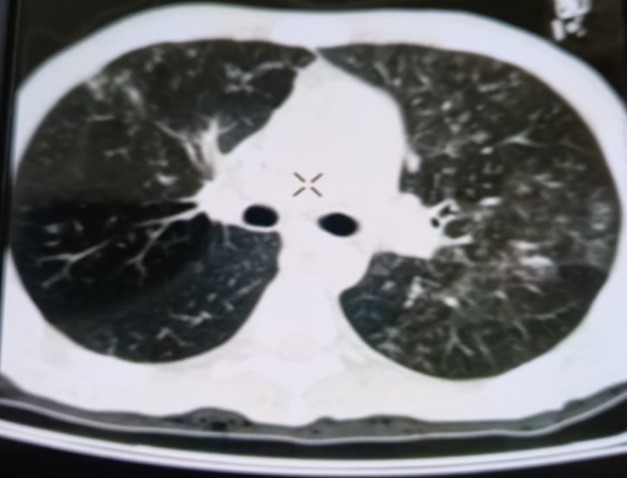

При проведении рентгенологического исследования органов дыхания в динамике спустя 2 недели с момента начала терапии данные компьютерной томографии высокого разрешения указали на следующие изменения: на фоне очаговой диссеминации в легких значительно увеличились по площади участки "матового стекла" в верхних долях обоих легких (описанные зоны неоднородные, сливные); площадь поражения легочной ткани - около 35-40%. В средних и нижних отделах легких с двух сторон выявлялись многочисленные перибронхиальные очаги до 3 мм в диаметре по типу «дерево в почках». В S 6 справа определялась зона альвеолярной инфильтрации. Выпот в плевральных полостях не определялся; внутригрудные лимфоузлы не увеличены. Заключение: признаки двусторонних полисегментарных интерстициально-инфильтративных, диссеминированных мелкоочаговых изменений легких, средняя вероятность вирусной пневмонии (в том числе COVID-19), в сочетании с диссеминированным процессом в легких (рис. 1-4).

Рисунок 1

Рисунок 2

Рисунок 3

Рисунок 4

Рис. 1-4. Компьютерная томограмма пациента Т., с ВИЧ: чередование участков «матового стекла» с диссеминированным процессом, инфильтрацией легочной ткани справа, наличие симптома «дерево в почках» (респираторный бронхиолит).